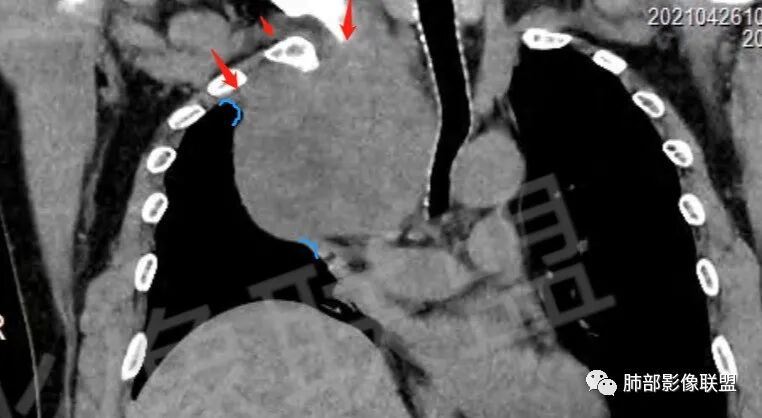

肿块把上腔静脉向前部推移,对肺内血管以及气管以推移为主,占位未见肺部血管供血,胸膜掀起处胸膜下脂肪间隙增宽,说明定位在肺外 SFT多为脏层胸膜起源,少部分壁层胸膜起源,壁层胸膜起源SFT不除外,但是胸膜掀起处胸膜下脂肪间隙增宽了,感觉SFT可能性比较小,这样囊变 AB区 纵膈神经起源的神经鞘瘤需要重点考虑,因为CT给的层不够,看不到肿瘤与椎间孔的关系,不敢确定,曾经病理提示高度考虑叶间起源肿瘤,肿瘤细胞呈短梭形细胞构成 不知道和神经鞘瘤是否符合!我重点考虑神经鞘瘤

边界清楚、光滑,D字征,与肺血管、支气管关系不密切,胸膜被掀起都提示肺外来源

上腔静脉受压前移

提示病灶来源于后方或纵隔外后方,

胸膜来源:孤立,大的边界清,首选SFT

纵隔:上腔静脉后方主要是膈神经,神经源性可以;后方局部与食道关系密切,食道来源肿瘤也可能,一般食道来源向前推移,这里推移方向不支持;气管受压,壁完整,软骨连续,气管单纯受压没有破坏,后方向内推移,不支持气管来源

粗大强化血管,主要看他起源,如果是来源肺动脉,肺内血管供血一是肺内二是脏层胸膜,肺内排除,只剩脏层胸膜SFT;如果这个是纵隔供血,那它可能是神经源性或者壁层胸膜,也可以是SFT比较少

从影像分析:SFT、神经鞘瘤鉴别可能大

强化方式:多均匀或不均匀明显强化,增强肿瘤内可见迂曲血管影(蛇纹血管等),肿瘤较大可见“地图样”强化。